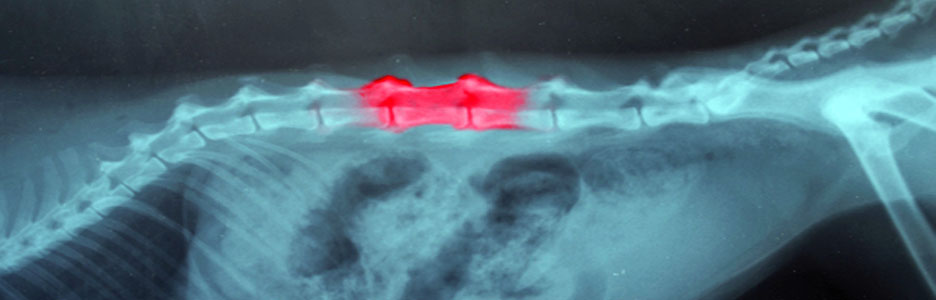

Spondylosis in dogs is characterised by the formation of osteophytes (bony spurs) that can bridge one vertebrae to another. It is commonly thought of as arthritis of the spine, however unlike arthritis this is a non inflammatory condition. It commonly affects the thoracic and lumbar vertebrae particularly at the thoracolumbar and lumbosacral junction.

The bony spurs which form are triggered by instability and they form to actually try and stabilise the joint, however as the bony spurs grow they can cause pain and discomfort.